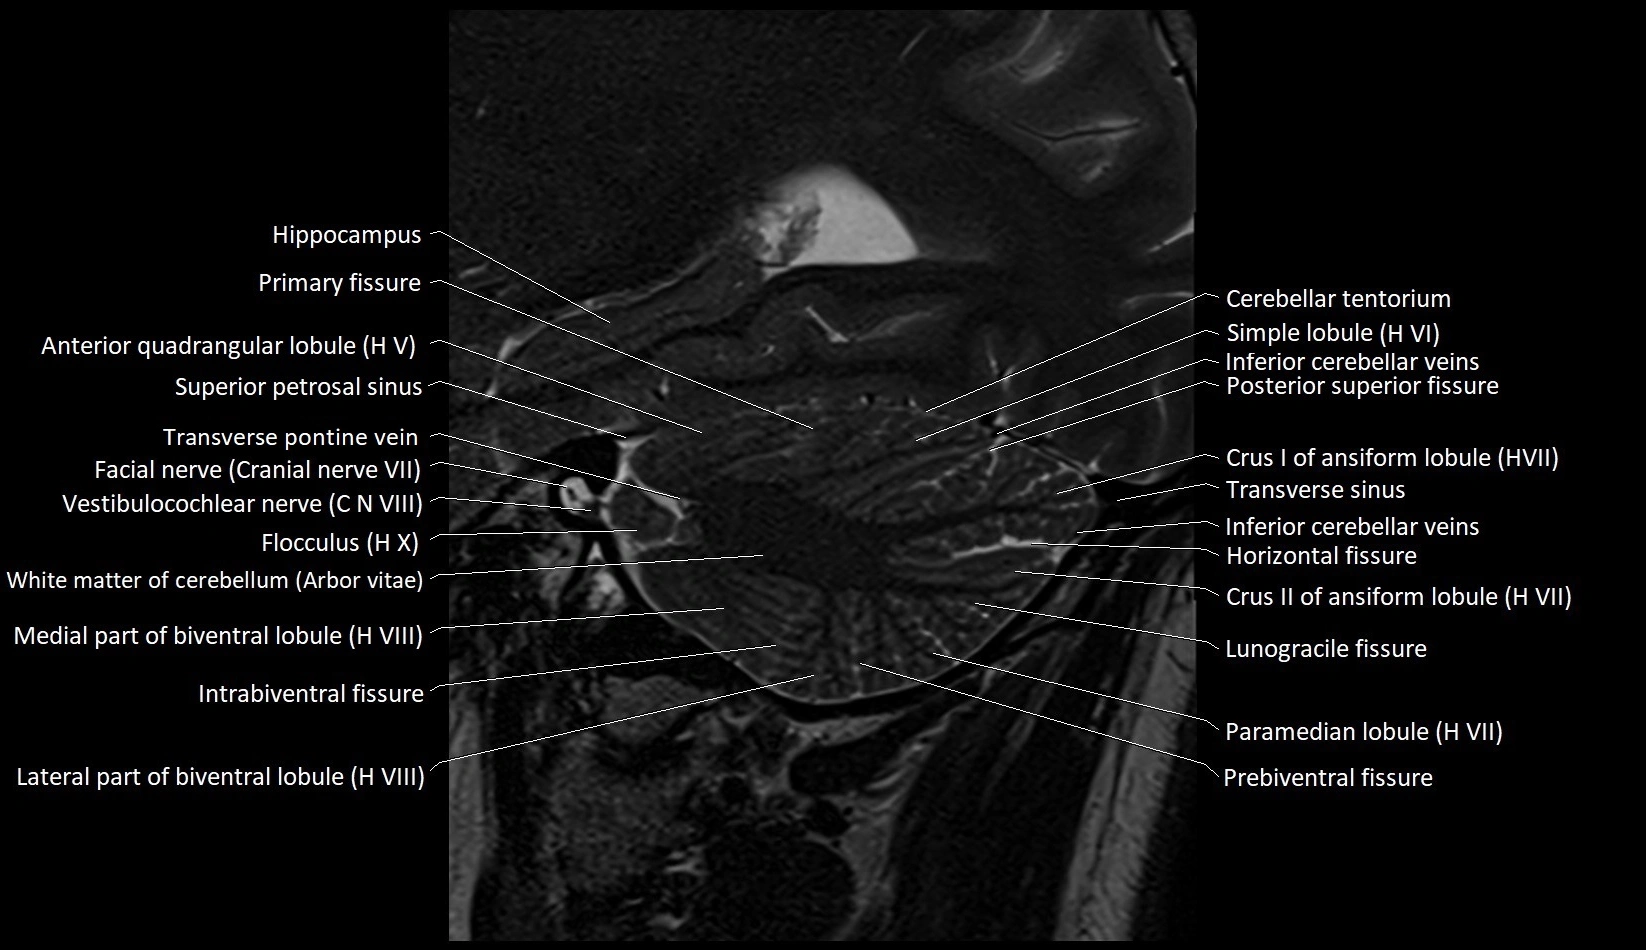

MRI images